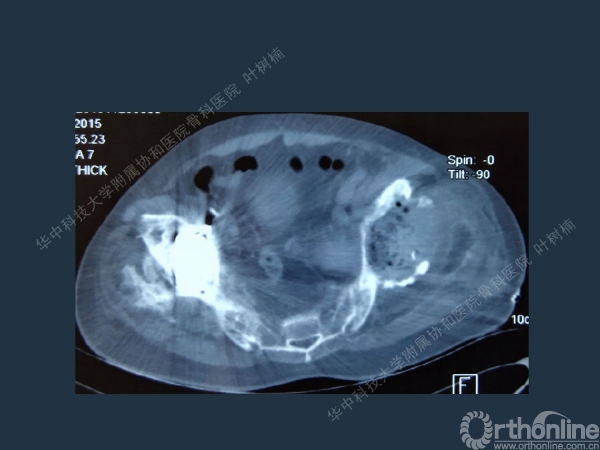

股骨侧翻修

髋臼缺损的处理